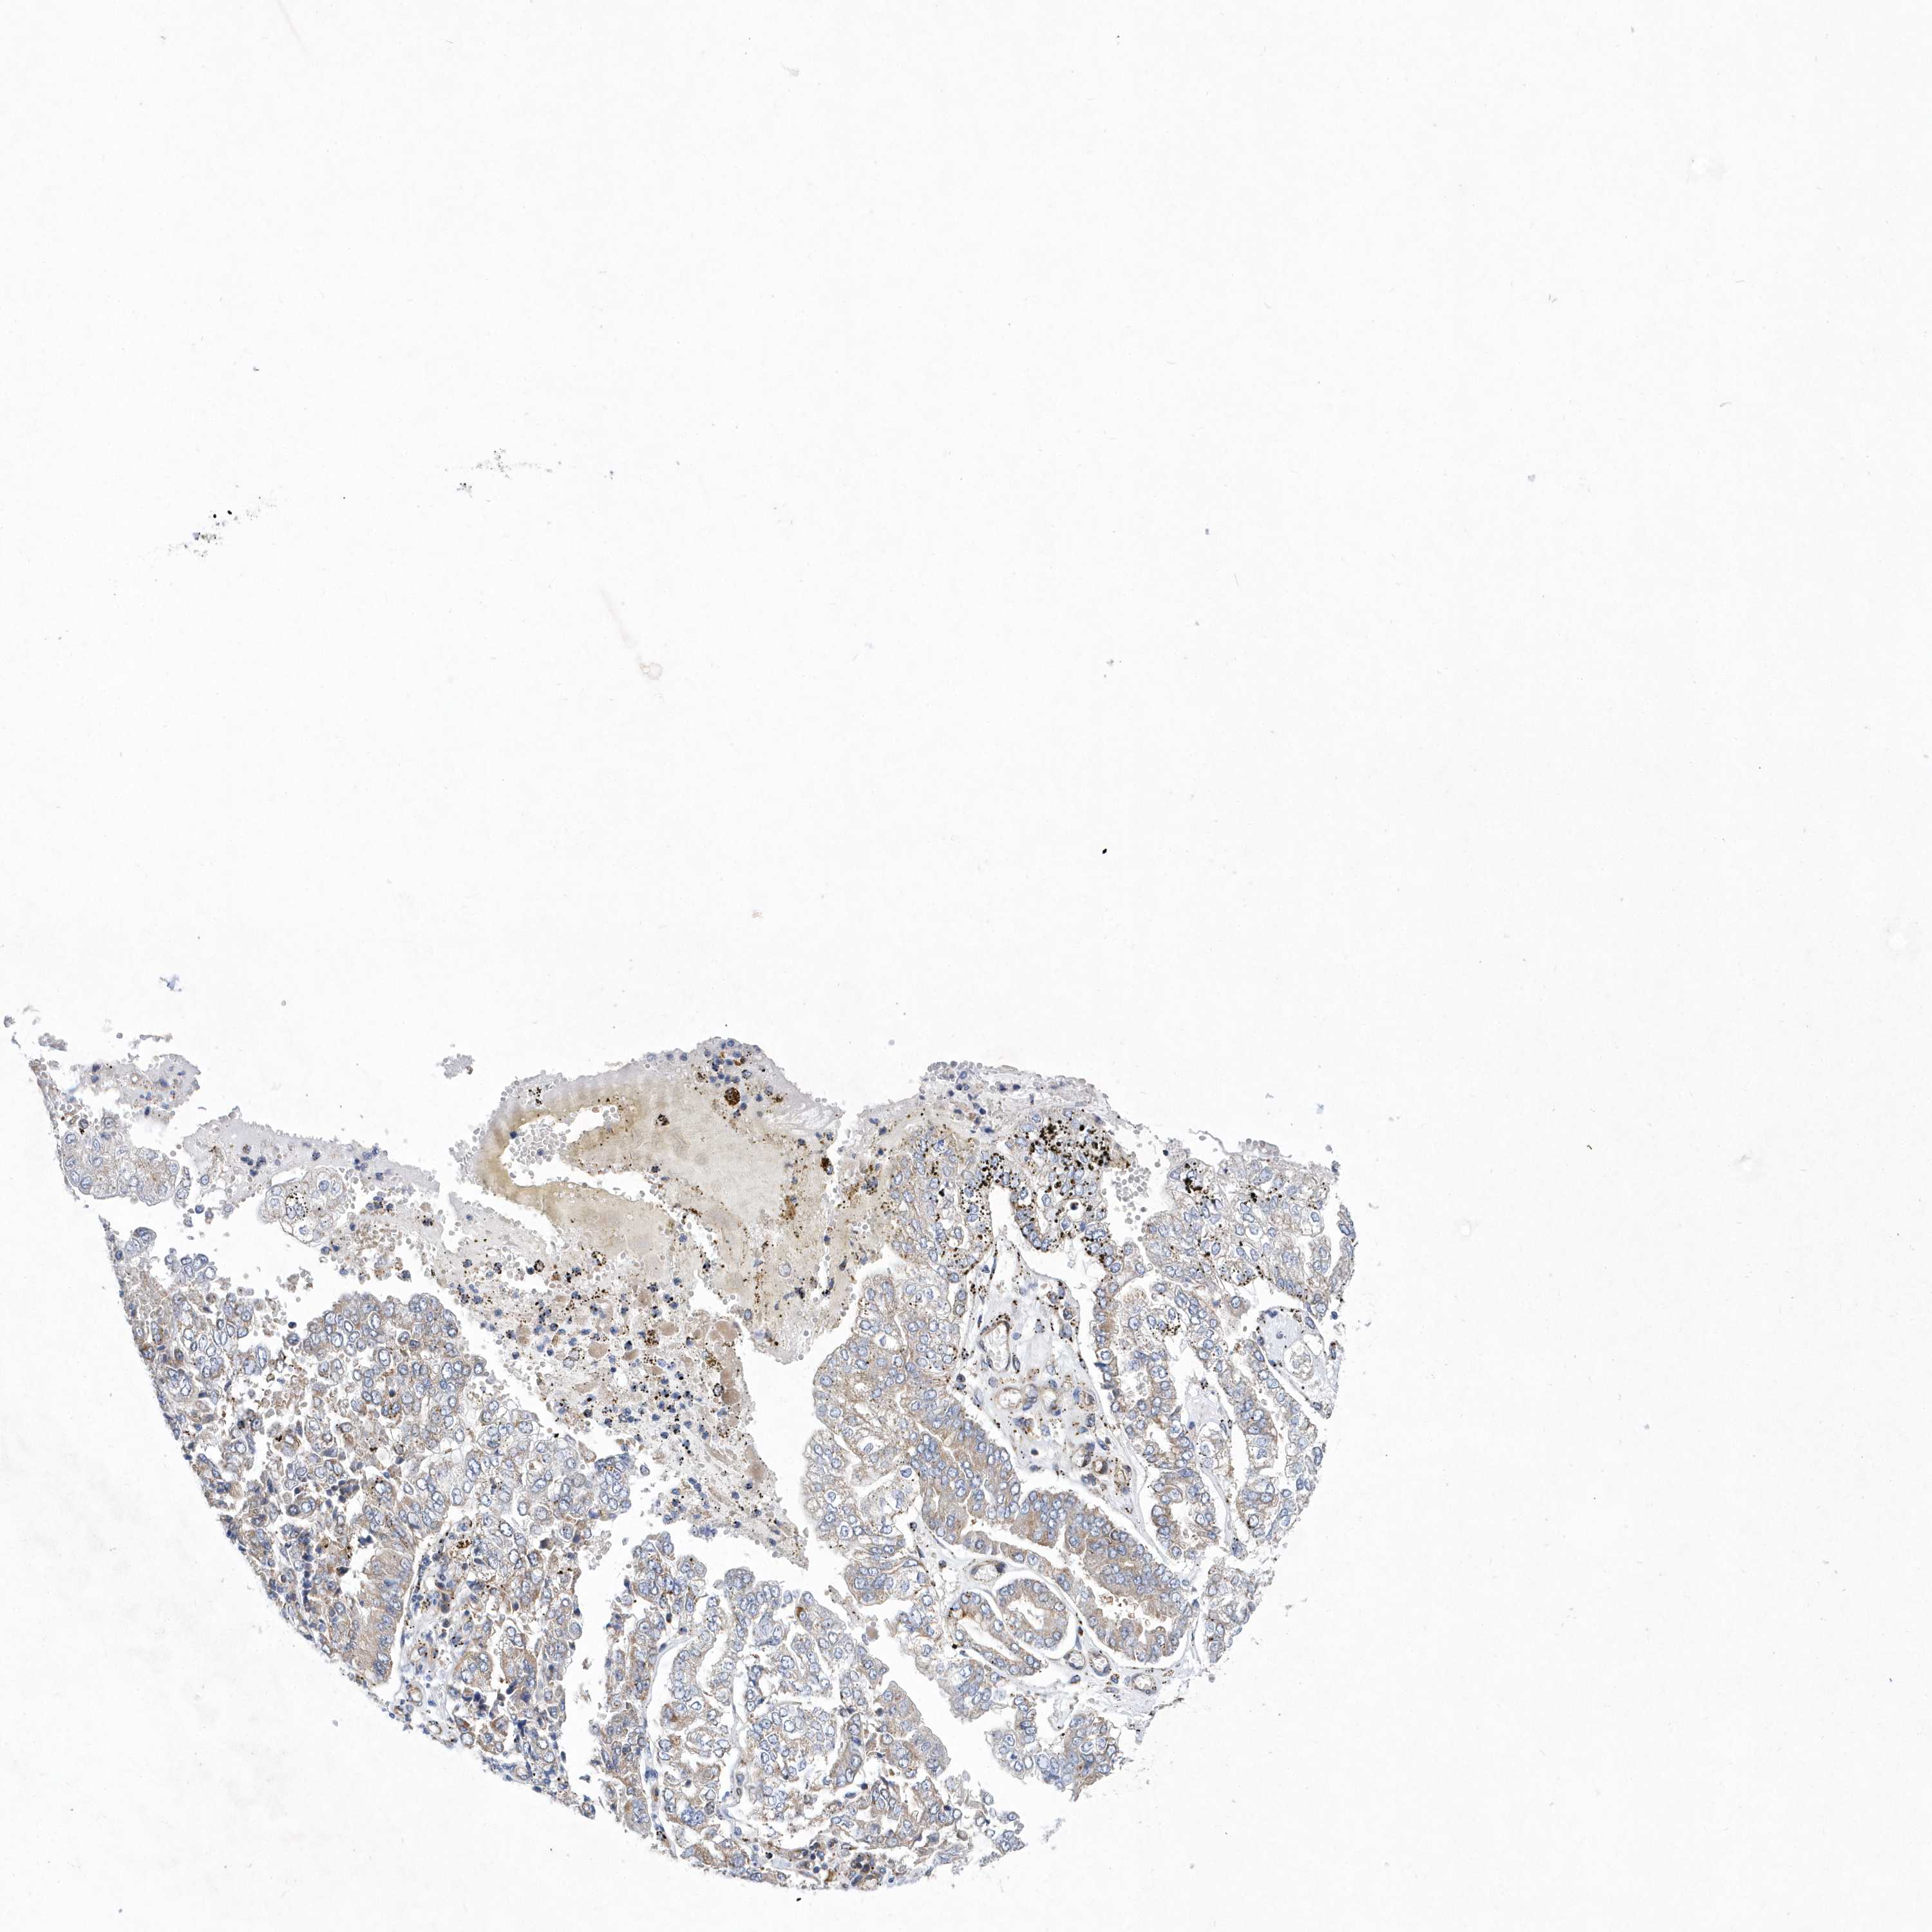

STOMACH CANCER - Protein expressioni

A mouse-over function shows sample information and annotation data. Click on an image to view it in a full screen mode. Samples can be filtered based on level of antibody staining by selecting one or several of the following categories: high, medium, low and not detected. The assay and annotation is described here.

Note that samples used for immunohistochemistry by the Human Protein Atlas do not correspond to samples in the TCGA dataset.

Antibody stainingi

Antibody staining in the annotated cell types in the current human tissue is reported as not detected, low, medium, or high, based on conventional immunohistochemistry profiling in selected tissues. This score is based on the combination of the staining intensity and fraction of stained cells.

Each image is clickable and will lead to virtual microscopy that enables deeper exploration of all samples and also displays staining intensity scores, fraction scores and subcellular localization as well as patient and tissue information for each sample.

Antibody HPA031172

Staining

High

Medium

Low

Not detected

Intensity

Strong

Moderate

Weak

Negative

Quantity

>75%

75%-25%

<25%

None

Location

Nuclear

Cytoplasmic/membranous

Cytoplasmic/membranous,nuclear

Adenocarcinoma, NOS